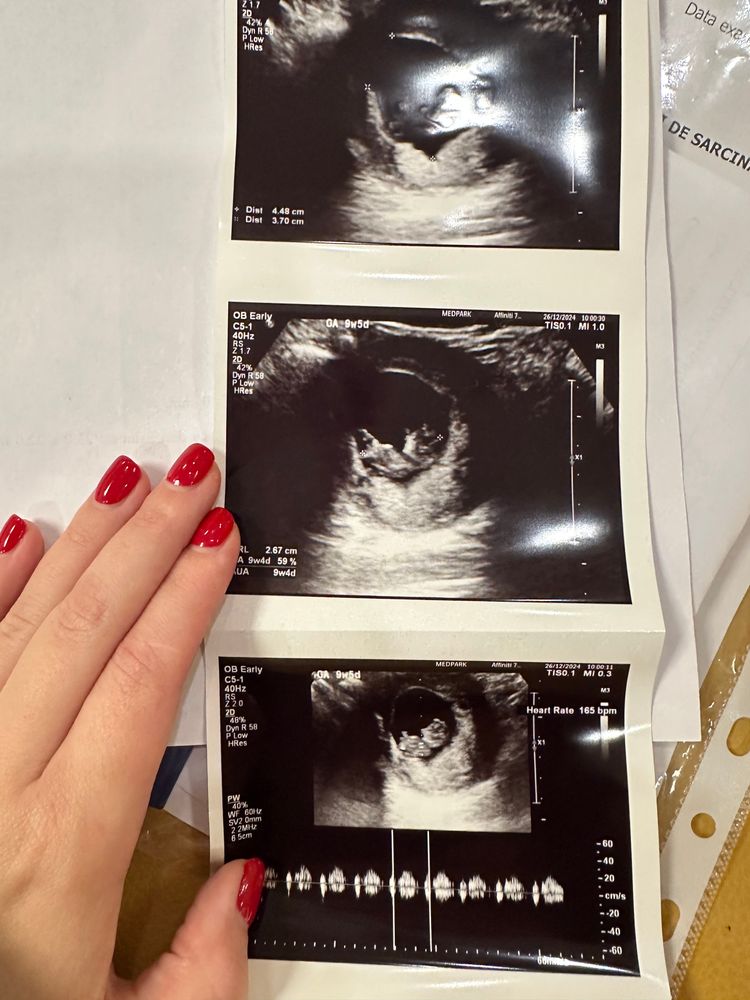

Просто объясните, КАК можно так замерять, я не понимаю. УЗИ вчера вечером: ктр 26, ПЯ 20*28. И собственно фото (вчера делала пост с ним уже):

УЗИ сегодня: ктр 27, ПЯ 37*45. Фото:

Это же какой ракурс и срез выбрали в первом случае? Как так можно мерить?

Врач сказала, что со вчерашней узисткой работают только по скорой. Сегодня узи делал мужчина, сказал, что вопросов у него нет к беременности, все хорошо🙏🏼